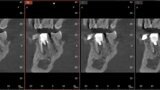

Fig. 6a: Post-op CBCT images of tooth #46 showing adequately obturated canals at all levels to the working length and sealing of the furcation defect.

Fig. 6b: Post-op CBCT images of tooth #46 showing adequately obturated canals at all levels to the working length and sealing of the furcation defect.

Fig. 6c: Post-op CBCT images of tooth #46 showing adequately obturated canals at all levels to the working length and sealing of the furcation defect.

Fig. 6d: Post-op CBCT images of tooth #46 showing adequately obturated canals at all levels to the working length and sealing of the furcation defect.

Fig. 6e: Post-op CBCT images of tooth #46 showing adequately obturated canals at all levels to the working length and sealing of the furcation defect.

Fig. 6f: Post-op CBCT images of tooth #46 showing adequately obturated canals at all levels to the working length and sealing of the furcation defect.

Fig. 6g: Post-op CBCT images of tooth #46 showing adequately obturated canals at all levels to the working length and sealing of the furcation defect.